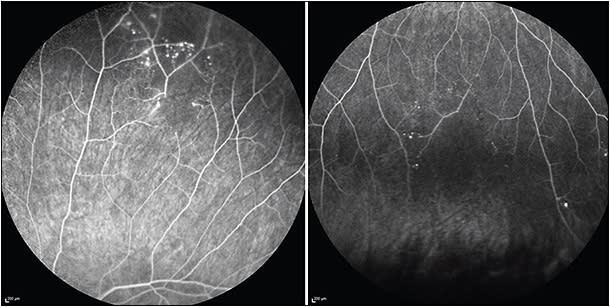

Visual field tests are a valuable tool to detect, quantify, and monitor visual field defects. These include altitudinal defects, paracentral scotoma, or central scotoma. Fundus FA is the diagnostic pillar in the workup for suspected Susac, as well as in the monitoring of treatment response and titration of therapy, even with normal funduscopy in asymptomatic patients. Susac syndrome may involve the retinal arteries from their large proximal branches up to small capillaries in the far periperhy. Fluorescein angiography can demonstrate BRAO already in the early frames, and BRAO can range from complete occlusion to only partial involvement. Arteriolar wall hyperfluorescence may accompany BRAO or be present in the absence of BRAO.12 Of note, AWH may not be evident in early photos but often becomes evident by mid and late frames. The extent of capillary nonperfusion becomes most clearly evident on late images. Recently, our group described microaneurysms as sequelae of peripheral ischemia in Susac syndrome (Figure 2).12 Accurate comparison between visits is of eminent importance in the monitoring of the disease. Therefore, all serial studies should to be done in exactly the same way (ie, showing the same areas at the same time). Also, the value of widefield FA has been shown lately, because peripheral findings might be missed with conventional FA.13